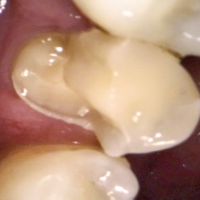

2. The Dexcam 3 Intraoral Camera.

An intraoral camera is a small camera that goes inside the mouth to take photos. This camera works great for taking large, clear pictures of single teeth.

An old amalgam filling that needs replacement.

This is a broken tooth in need of a large filling or a crown.